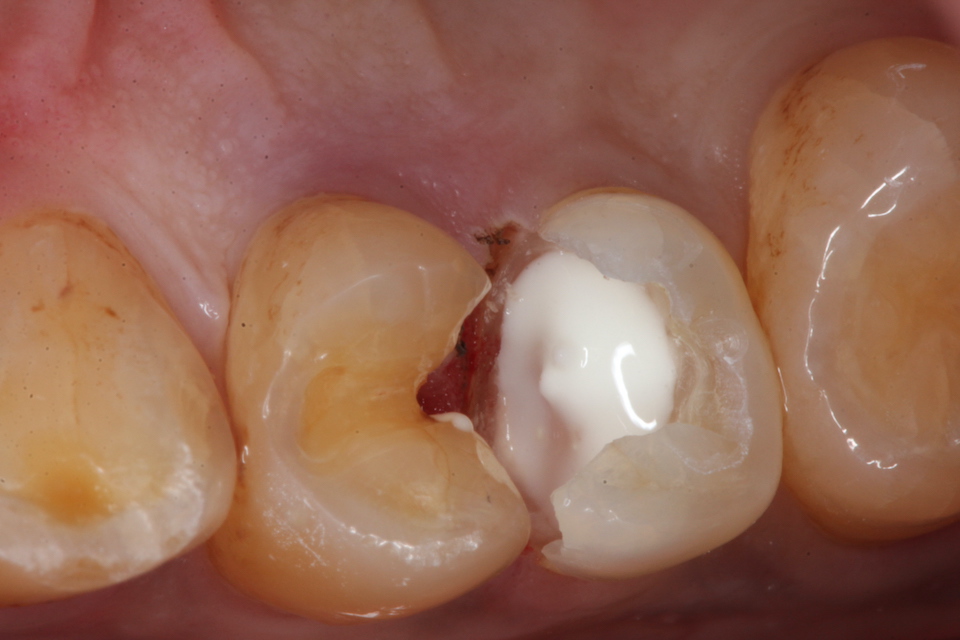

下顎7番の頬側歯茎部カリエスの原因 2025.06.04